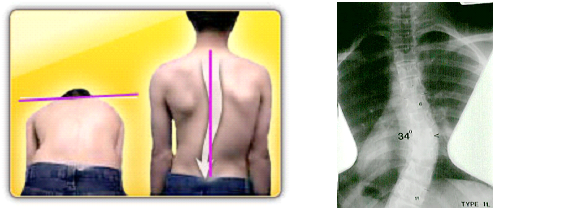

Η ιδιοπαθής σκολίωση των εφήβων είναι η άγνωστης αιτιολογίας οργανική σκολίωση που την ανακαλύπτουμε στις ηλικίες από 10 έως 18 ετών. Είναι ο πιο συχνός τύπος σκολίωσης και παρά την εκτεταμένη και πολύχρονη επιστημονική έρευνα δεν έχει βρεθεί o αιτιοπαθολογικός μηχανισμός. Υπάρχει σαφώς γενετική βάση και πρόσφατα έχει βρεθεί μια ομάδα γονιδίων που φαίνεται ότι ευθύνεται για την επιδείνωση της κατάστασης.

Αφορά κυρίως τα κορίτσια σε ποσοστό 7 προς 1, δηλαδή σε 7 κορίτσια με σκολίωση αντιστοιχεί 1 αγόρι με σκολίωση. Στο 30% των περιπτώσεων κάποιο άλλο μέλος της οικογένειας έχει ιστορικό σκολίωσης…